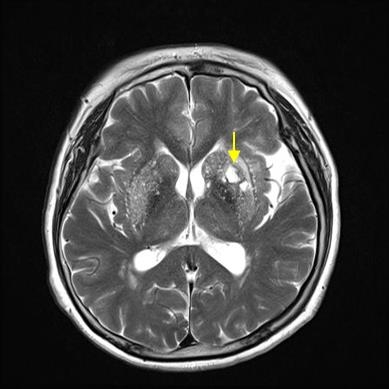

뇌의 혈관이 막혀 해당 영역의 뇌 일부가 죽는 상태입니다. 뇌혈전증과 뇌색전증이 있습니다. 심한 협착으로 인해 뇌로 가는 혈관이 완전히 막히거나 혈류가 현저히 감소하면 뇌 조직의 이 부분이 죽고 결국 녹습니다. 뇌연화증은 뇌세포가 죽어 부드러워지는 현상이고, 뇌성마비는 뇌경색으로 인해 뇌세포가 죽어가는 현상이다. 요약하자면 뇌혈관이 막혀 눈앞의 뇌조직이 괴사하는 질환이다.

후두엽의 혈관이 막히면 첫 번째 증상은 시력 저하 또는 복시입니다. 또한 단순한 시력 상실보다는 텍스트나 사물이 겹쳐서 잘 보이지 않는 증상이 있다고 합니다. 따라서 일반적으로 시력은 점차적으로 저하되지만 뇌경색의 경우에는 시력이 급격히 저하되거나 한쪽 눈이 전혀 보이지 않을 수 있습니다.